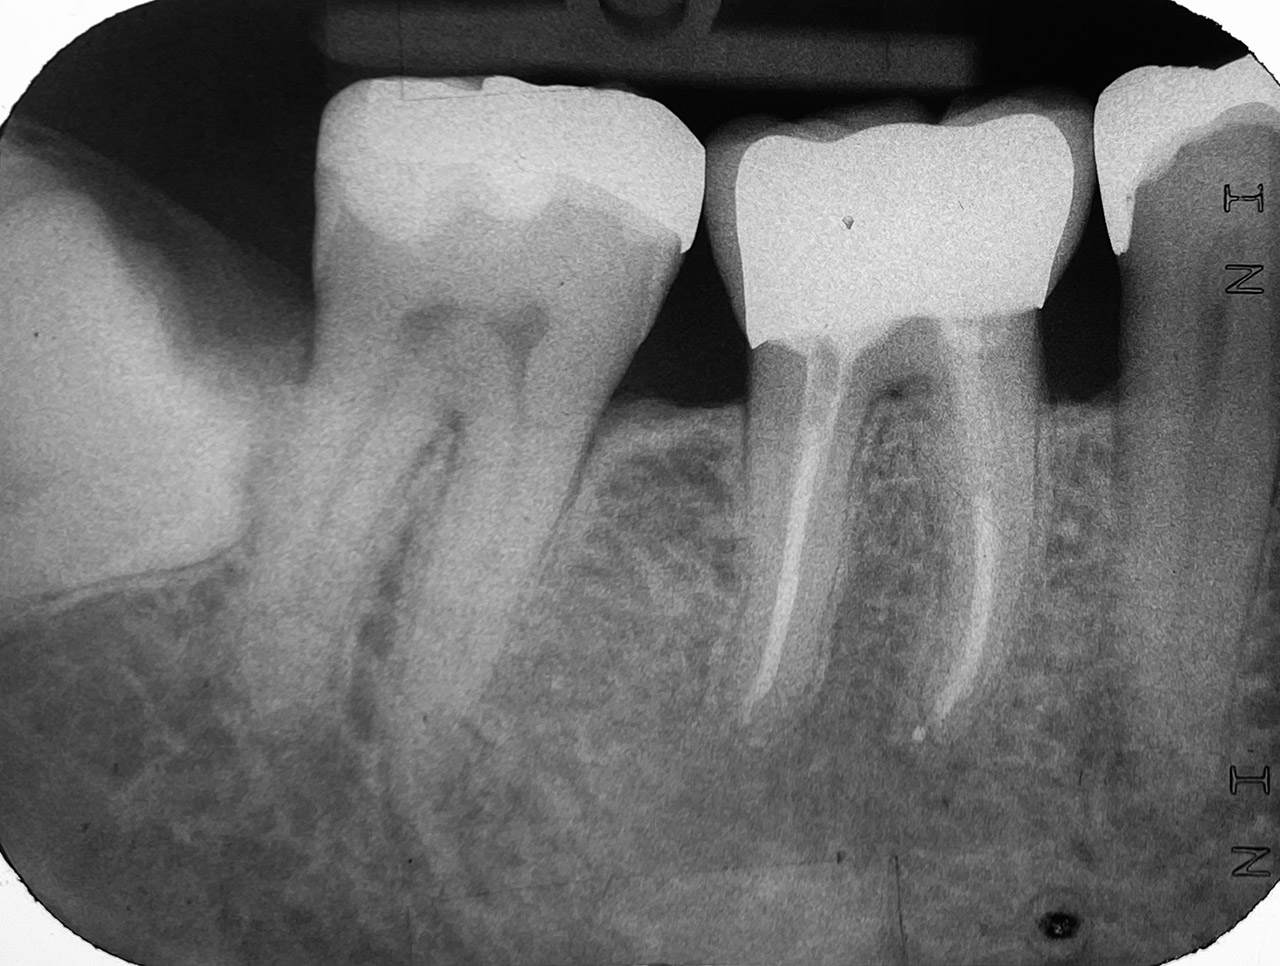

Wurzelbehandlung/Endodontie:

Massiver Paro-/Endodefekt bei den Zähnen 38&37. Extraktion von 38 (Weisheitszahn) und Wurzelbehandlung von 37 (4 Kanäle). Defekt vollständig ausgeheilt.